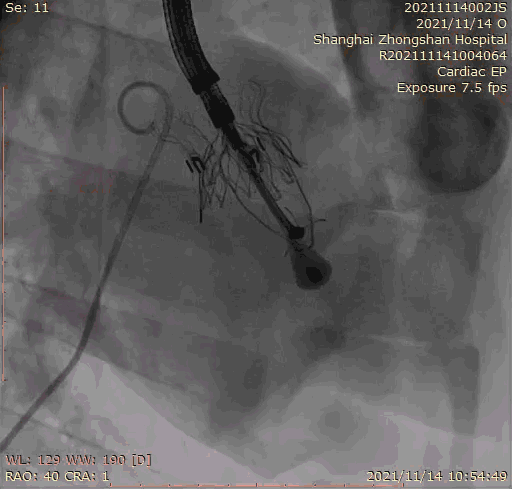

本次臨床前研究經(jīng)右側頸靜脈置入LuX-Valve Plus輸送系統(tǒng)可調彎鞘管,在DSA及超聲引導下將人工三尖瓣瓣膜植入到原有三尖瓣位置,利用獨特的錨定技術將人工瓣膜支架可靠固定在預定的位置。

上海中山醫(yī)院葛均波院士、錢菊英院長、周達新教授、潘文志教授、潘翠珍教授、李偉教授共同完成此次臨床前研究。術后葛均波院士對Lux-Valve Plus的器械操作性能給予了高度評價,DSA和超聲影像也顯示出在本次研究中Lux-Valve Plus的安全性和有效性俱佳。